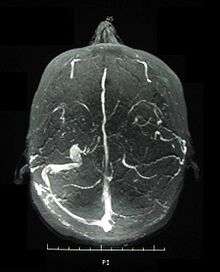

Visual acuity, or color vision loss with concurrent mucocutaneous lesions and/or systemic Behçet's symptoms should raise suspicion of optic nerve involvement in Behçet's disease and prompt a work-up for Behçet's disease if not previously diagnosed in addition to an ocular work-up. Diagnosis of Behçet's disease is based on clinical findings including oral and genital ulcers, skin lesions such as erythema nodosum, acne, or folliculitis, ocular inflammatory findings and a pathergy reaction. Inflammatory markers such ESR, and CRP may be elevated. A complete ophthalmic examination may include a slit lamp examination, optical coherence tomography to detect nerve loss, visual field examinations, fundoscopic examination to assess optic disc atrophy and retinal disease, fundoscopic angiography, and visual evoked potentials, which may demonstrate increased latency. Optic nerve enhancement may be identified on Magnetic Resonance Imaging (MRI) in some patients with acute optic neuropathy. However, a normal study does not rule out optic neuropathy. Cerebrospinal fluid (CSF) analysis may demonstrate elevated protein level with or without pleocytosis. Imaging including angiography may be indicated to identify dural venous sinus thrombosis as a cause of intracranial hypertension and optic atrophy.